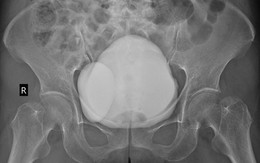

bàng quang

Sống khỏe 2024-04-15T11:21:00Bệnh nhân đi khám do bị sốt cao, ho đờm, đau họng. Thế nhưng kết quả chụp CT ổ bụng tình cờ phát hiện bệnh nhân mắc căn bệnh được ví như "quả bom" trên bàng quang.

Sống khỏe 2023-11-14T15:43:00Khi cơ thể xuất hiện các triệu chứng tiểu buốt, tiều rắt kéo dài, anh V đã đi khám và được bác sĩ kết luận mắc ung thư bàng quang.

Sống khỏe 2019-10-22T12:33:00Đi tiểu ra máu là triệu chứng đầu tiên cảnh báo căn bệnh ung thư bàng quang. Ung thư bàng quang có liên quan tới thói quen hút thuốc và một số yếu tố nguy cơ khác.

BS cảnh báo ung thư bàng quang đã gặp ở người trẻ: Đi tiểu gặp dấu hiệu này phải khám ngay